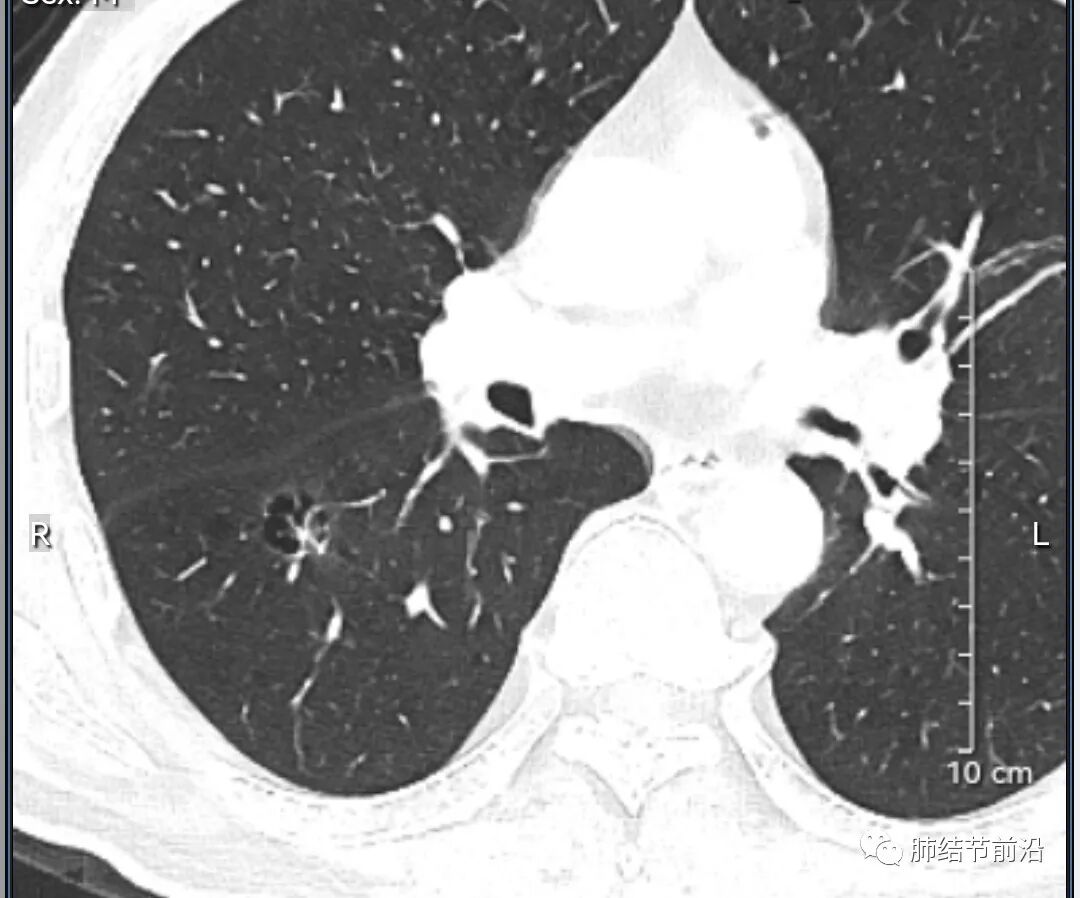

男性,67岁,重度吸烟史。CT发现右下肺囊腔。来看一下这个CT的特点:

该囊腔形态非常有特点,和常见的圆形肺大泡有很大的区别。

1.囊腔中央实性成分,周围有磨玻璃影。

2.囊腔中央有血管。

3.囊腔外周有分叶形态。

4.囊腔有胸膜牵拉。

出现这几种形态,CT可以确认恶性的腺癌。这个囊腔形成的机制,为肿瘤实性成分堵塞细支气管形成活瓣,肺泡内压力增高破裂行成,因此肺内血管成分保留。由于肺泡压力增高,而呈分叶状。另外,也有肿瘤的胸膜牵拉这一特点。

囊腔周围磨玻璃+囊腔中央血管为特征性表现。如果持续存在,几乎可以100%确认为早期肺腺癌。

建议患者手术切除,术后病理为浸润性腺癌,腺泡型,部分为实体型。IA1期,术后不用治疗。